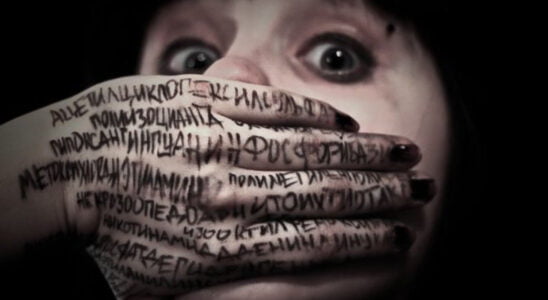

Hippopotomonstrosesquippedaliophobia nedir?

Hippopotomonstrosesquippedaliophobia, sözlük anlamı olarak “uzun kelimelere korku” olarak tanımlanır. Bu, kişinin uzun kelimelerden korkmasına veya bunlardan rahatsız olmasına neden olan bir fobidir. Uzun kelime korkusunun semptomları nelerdir? Hippopotomonstrosesquippedaliophobia olarak bilinen…